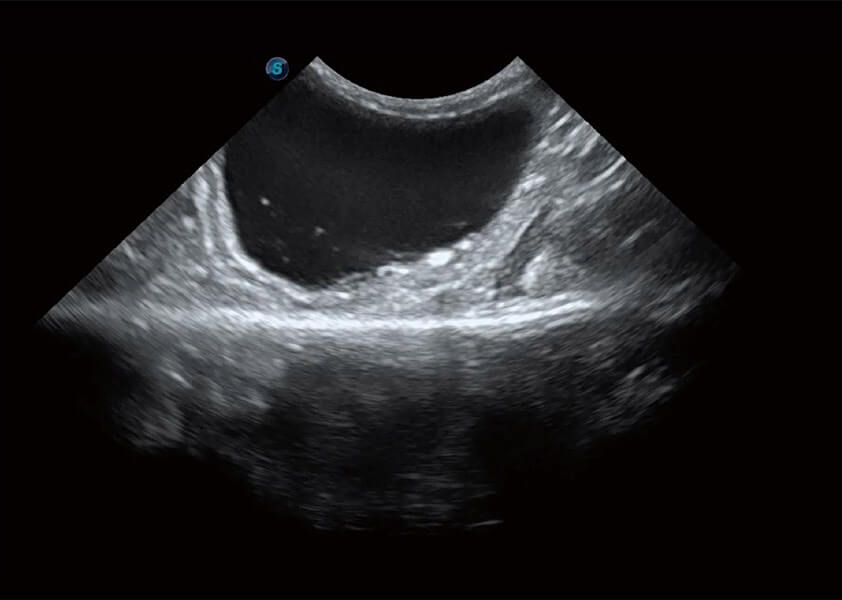

ProPet 60 作为一款高端台式动物超声设备,为动物医生的日常诊断提供了一系列贴合动物临床需求、解决临床实际问题的高级成像功能。凭借全系列高清探头,满足医生对腹部、心脏、生殖、浅表、肌骨等成像的所有需求,切实帮助您提升检查效率,提高诊断信心。

动物是人类最亲密的朋友和最值得信赖的伙伴。16877太阳集团也一直致力于探索动物专用的超声影像解决方案。 全新推出的ProPet系列,是16877太阳集团在动物超声影像智能化、专业化、精准化的一次跨越式革新。动物不能用言语来表述自己的不适,通过超声影像,ProPet系列搭建了动物医生与不同物种沟通的“桥梁”,为动物医生注入了“治愈之力”。